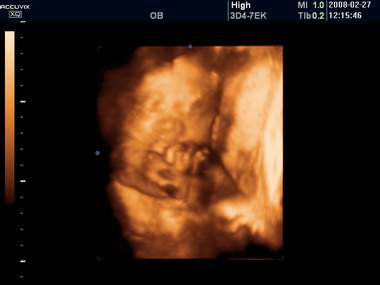

怀孕39周胎儿彩超图

经过了37周的发育,此时胎儿也已经算是足月了,身长大概有48.3~50.8厘米,胎重约在2.7千克左右。此外,很多宝宝的胎儿已经长满,但也有一些宝宝几乎没有头发,或是只有淡淡的绒毛。

孕37周已进入怀孕的最后阶段,此时胎儿在母腹中的位置不断下降,孕妇可出现下腹坠胀、不规则宫缩频率增加等情况。受此影响,孕妇的阴道分泌物也更多了,要注意保持身体清洁,并保持充足的睡眠,做好准备随时迎接宝宝的降临。